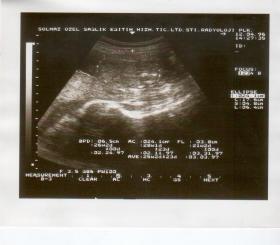

W Europie badanie płodu w kierunku wykrycia nieprawidłowej liczby chromosomów  wykonuje się głównie przy pomocy usg i testu PAPP-A.Nevit Dilmen/Wikipedia W Europie badanie płodu w kierunku wykrycia nieprawidłowej liczby chromosomów wykonuje się głównie przy pomocy usg i testu PAPP-A.